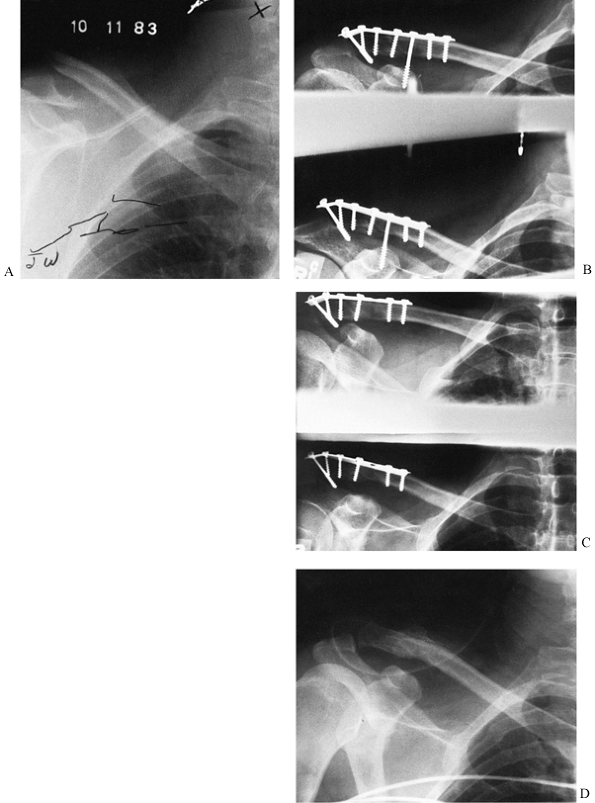

Figure 27.4. Nonunion of a distal clavicle fracture. A:

A 25-year-old skier suffered a displaced fracture of the distal third of his clavicle. Nonoperative treatment was unsuccessful. He had pain and an unsightly deformity at 6 months. The atrophic nonunion was completely mobile. B: Internal fixation was performed using a third-tubular plate. There is an interfragmentary screw across the fracture site and a coracoclavicular screw. The most distal screw runs obliquely through the longest portion of the acromion. A cancellous bone graft was applied. C: At 8 weeks, the coracoclavicular screw was removed. Before this, the patient had been allowed pendulum exercises with abduction of his shoulder to only 90°. After screw removal, full range of motion was instituted. D: A radiograph 1.5 years after operative intervention shows that the plate has been removed, and there is solid union of the nonunion. |